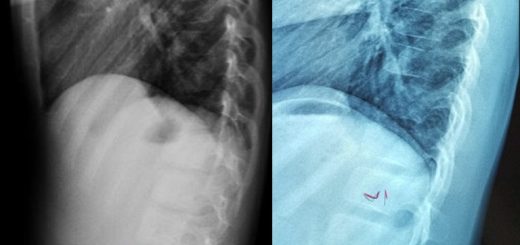

Neglect of Spinal Healthcare

• Next story Shortness of Breath due to Hunching (Hyperkyphosis)